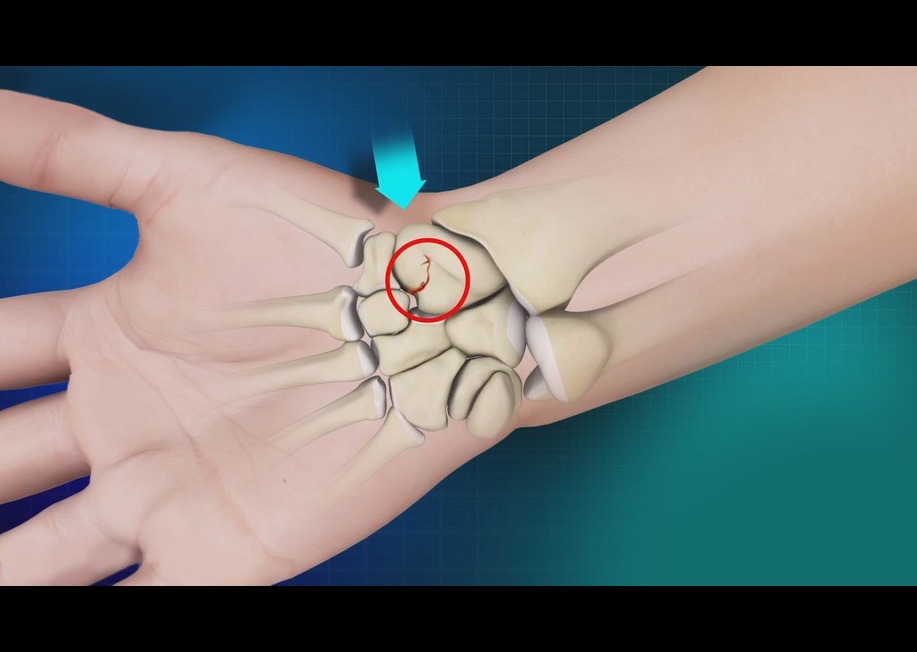

شکستگی استخوان اسکافوئید ( Scaphoid ) رایج ترین شکستگی استخوان های مچ است و تشخیص و درمان شکستگی های مچ اغلب دشوار است. این شکستگی در افراد بزرگسال جوان در اثر افتادن با دستان باز ( Falling On Outstretched Hand ) اتفاق میفتد( شکل ۱ ) . این شکستگی ممکن است که نادیده گرفته شود و فرد آن را بعنوان کشیدگی تاندون در نظر بگیرد یا ممکن است در اوایل در عکس رادیولوژی ساده قابل مشاهده نباشد . این شکستگی ممکن است دچار جوش نخوردگی شود یا اینکه بد جوش بخورد که که حرکات دست را دستخوش تغییر میکند و میتواند باعث درد و کاهش دامنه حرکتی و قدرت و آرتروز زودهنگام مچ دست شود . بهبودی، اغلب آهسته است و در بعضی موارد ممکن است جوش نخورد. برای احتیاط، در مراحل اولیه ، دست در گچ قرار میگیرد و دوباره بعد از چند هفته عکس رادیولوژی ساده میگیرند اگر شکستگی در عرض یک هفته بعد از بی حرکتی تشخیص داده شود جوش نخوردن میتواند پیشگیری شود. اگر شکستگی در کمر استخوان رخ دهد خونرسانی بخش پروکسیمال مختل شده و ممکن است باعث مرگ بافت استخوانی درنتیجه فقدان خونرسانی شود. ( شکل ۲ ) . عوارض بلند مدت میتواند باعث بروز آرتروز این ناحیه شود.

( شکل ۲) : خونرسانی استخوان اسکافوئید و مرگ بافت آن در اثر اختلال خونرسانی.

شاخه های شریان رادیال از سطوح لبه پشتی یک سوم دیستال و سطح خارجی کف دستی وارد اسکافوئید ( Scaphoid ) میشوند ( شکل ۴ ) . خونرسانی یک سوم پروکسیمال اسکفوئید از شریانهای بین استخوانی تامین میشود و مستعد ریسک برای نکروز استخوانی (مرگ بافت استخوانی درنتیجه فقدان خونرسانی) است.